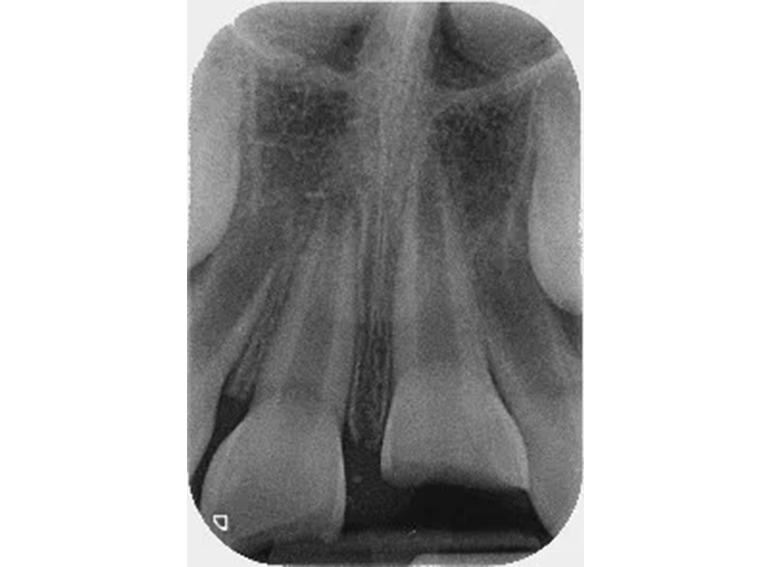

Surgical extrusion, root canal and apexification treatment of UL1 and composite build ups of UR1 and UL1 following dental trauma.